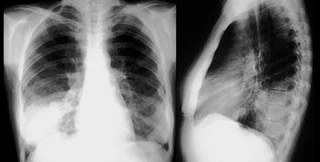

Министерство здравоохранения подтверждает 80 случаев смерти от пневмонии. Об этом в эфире Первого национального телеканала сообщила заместитель главного санитарного врача Людмила Мухарская.

"По последним данным умерло от пневмонии, не от гриппа и ОРВИ, а от пневмонии 80 людей", - цитируют Мухарскую "Українські новини".

Ранее Министерство здравоохранения официально подтвердило 71 случай смерти от гриппа и ОРВИ. Умерли 66 взрослых, трое детей и двое беременных.